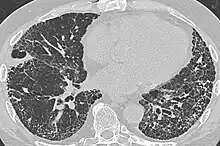

In radiology, honeycombing or "honeycomb lung" is the radiological appearance seen with widespread pulmonary fibrosis[1] and is defined by the presence of small cystic spaces with irregularly thickened walls composed of fibrous tissue. Dilated and thickened terminal and respiratory bronchioles produce cystic airspaces, giving a honeycomb appearance on chest x-rays. Honeycomb cysts often predominate in the peripheral and pleural/subpleural lung regions regardless of their cause.

Subpleural honeycomb cysts typically occur in several contiguous layers. This finding can allow honeycombing to be distinguished from paraseptal emphysema in which subpleural cysts usually occur in a single layer.